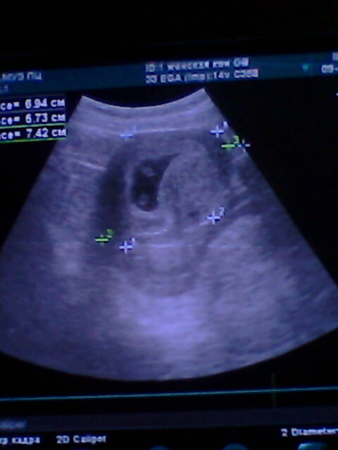

я вижу 2х))))))а что врачь сказал?

если срок стоит как на значке, то ребенок в это время не выглядит точкой. Возможно просто срез. Мне про двойню сразу сказали, это очень существенный нюанс при Б, и если бы врач увидел двоих, то 100%предупредил и обрадовал и записал в бланк показатели обоих.

это УЗИ мне делали 9 числа,тогда было 7 неделек

я сначала тоже думала что это срез.... но не кажется, что предпологаемая "голова" далековато от "попы"? Какой то он длиннючий получается.... конечно у меня муж 195 см, но сомневаюсь что это показатель.........

ДВА!!!!!!!!!!!!!!! на однояйцевых похоже!!!!!!!! )))))))))))))))

Может 2-а, а может просто в срез попали головной и ножной конец эмбриончика)))

мне это Узи делали на 7 недельке.....

похоже конечно на двойню,скорее всего один лялик))просто на таком сроке,он уже не точка, а как запятая и уже похожа на человечика))

я тоже вижу 2.... Мне угрозу ставили, так что важнее было посмотреть есть отслойка или нет,ее небыло,я от радости об остальном и спросить забыла.... мамаша........

Странная врач какая-то-неужели сложно сказать?! У меня на УЗИ сразу сказала. Причем, тоже было 2 горошинки: 1 эмбриончик, а рядом желтое тело, так что, возможно, у тебя тоже самое. Как бы там ни было, главное - чтобы здоровенький!!!! Удачи!!!!

Что плодное яйцо одно, у эмбриона сердечко стучит, все в порядке. Я и успокоилась, пока к УЗИ не присмотрелась

По-моему, 2 лялечки. Поздравляю!!! Растите!!!

похоже на двух однояйцевых! сдай ХГЧ и все понятно будет!

2! ну я прям уверенна что 2! у вас и диаметр плодного яйца в 4 недели большой был.

у меня один малыш. сейчас такой срок что трудно ошибиться